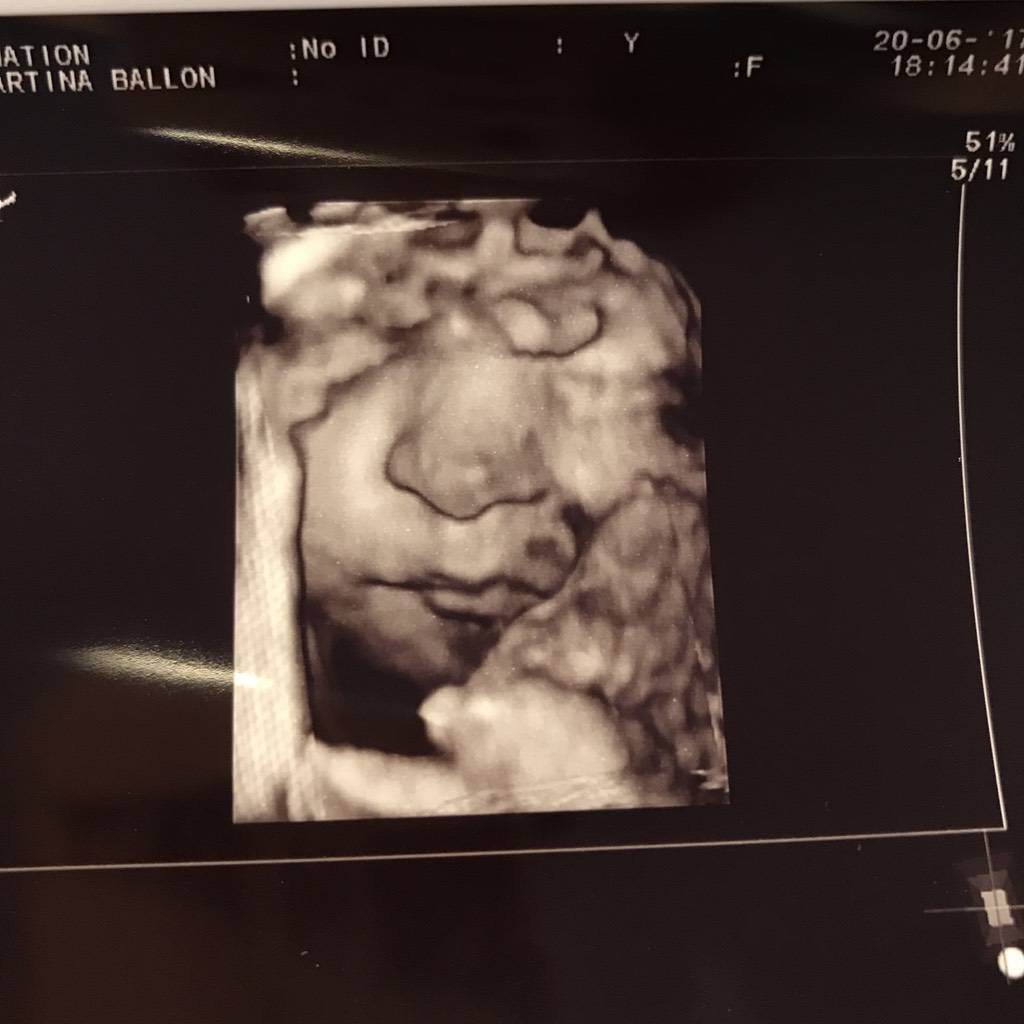

@puppy2015 und natürlich auch all die anderen lieben Mädels hier: wir haben heut endlich mal Fotos bekommen! Ella hat sich ja bis jetzt immerzu versteckt hihi! Sie ist bereits 46 cm groß und 2100 g schwer und alles sieht suuuuper aus! Auch ein Bauchifoto lass ich da! Mei ich bin so stolz dass ich auch endlich eine Kugel hab!!! Sie ist so wunderschön und ich bin sooo dankbar dass wir dieses Wunder erleben dürfen!